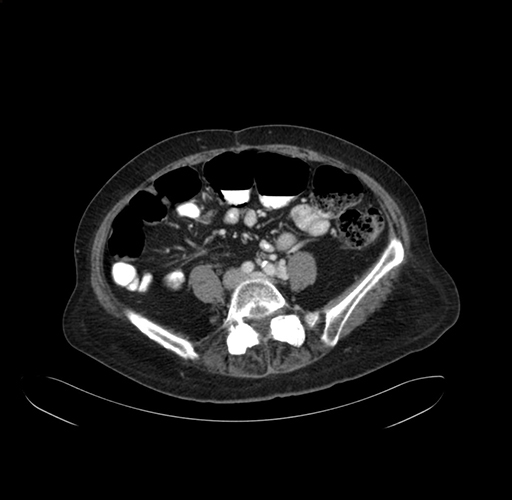

Pre-Chemo: Axial Venous

Axial Venous